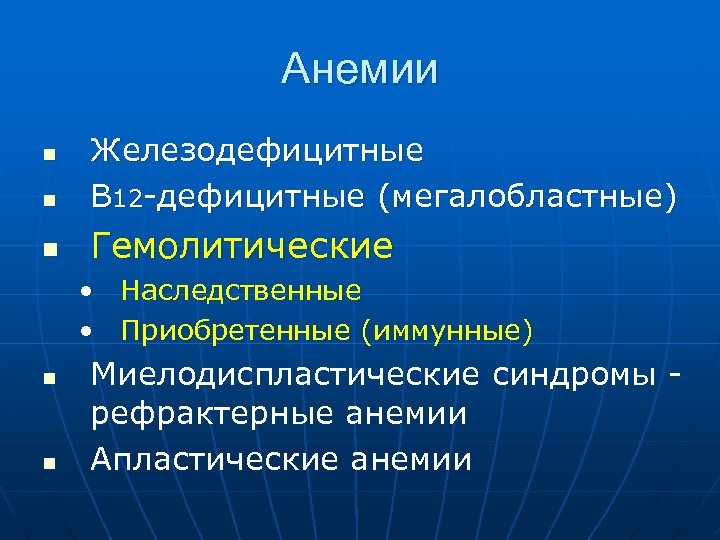

Анемии n Железодефицитные В 12 -дефицитные (мегалобластные) n Гемолитические n • Наследственные • Приобретенные (иммунные) n n Миелодиспластические синдромы рефрактерные анемии Апластические анемии